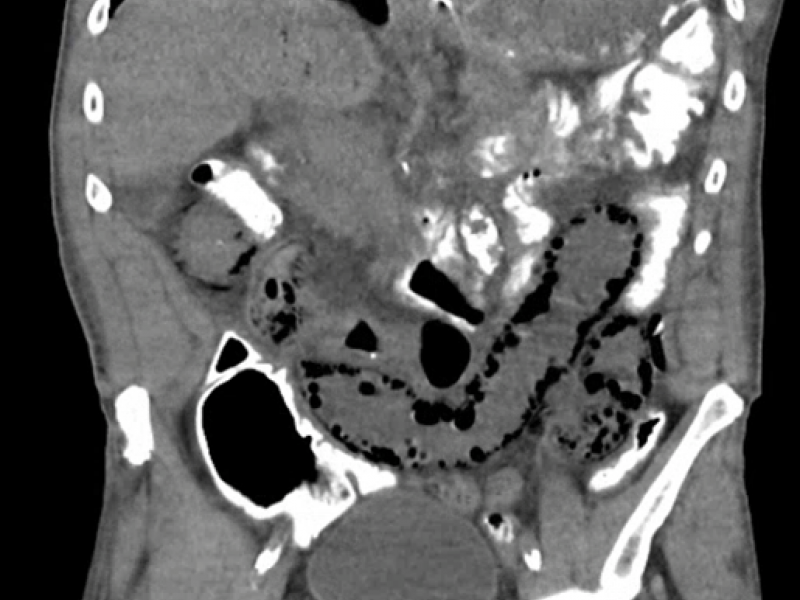

A 68 yo M with a past medical history of HTN, CKD, CAD and